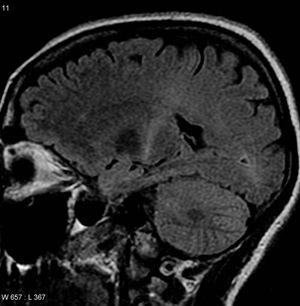

ALS 증상은 다른 다양한 질병이나 장애의 증상과 유사할 수 있으므로, 다른 상태의 가능성을 배제하기 위해 적절한 검사를 수행해야 한다. 이러한 검사 중 하나는 근육의 전기적 활동을 감지하는 근전도 검사(EMG)이다. 특정 근전도 검사 결과는 ALS 진단을 뒷받침할 수 있다. 또 다른 일반적인 검사는 신경전도 검사 (NCV)를 측정하는 것이다.[85] NCV 결과의 이상은 ALS가 아닌 말초 신경병증 또는 근육병증을 시사할 수 있다. 자기 공명 영상(MRI)은 초기 단계의 ALS 환자에게는 정상인 경우가 많지만, 척수 종양, 다발성 경화증, 목의 추간판 탈출증, 척수공동증, 또는 경추 척추증과 같이 증상을 유발할 수 있는 다른 문제의 증거를 나타낼 수 있다.[5]

;MRI

근위축성 측삭 경화증 진단에 적극적으로 기여하는 자기 공명 영상(MRI) 소견은 아직 밝혀지지 않았다. 다른 질환을 배제하기 위해 두부 MRI나 척수 MRI를 시행한다.